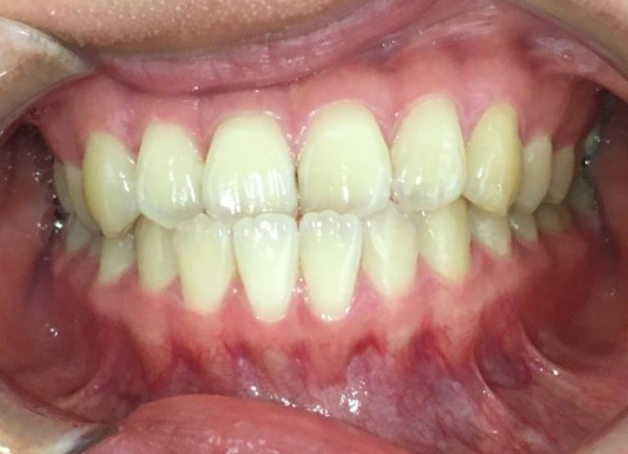

20代女性「下の前歯が上の前歯に被さっている」上下の歯の位置が逆になっている「反対咬合」を、マウスピース矯正装置「インビザラインGO」で費用を抑えて改善した症例

拝見したところ、下の前歯が上の前歯より前に出ている「反対咬合」でした。

反対咬合になっているのは前歯のみで、奥歯の噛み合わせや骨格は問題なかったため、前歯の傾きや位置を調整することで改善できると診断しました。

上下の前歯が正常な位置関係になり、美しい歯並びになりました。噛み合わせも問題ありません。